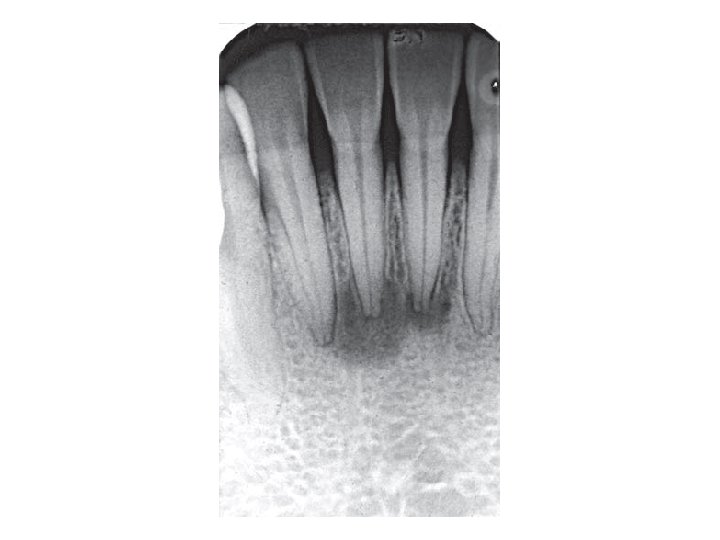

Akute Apikale Parodontitis • PRIMER Symptome: Akute Entzündung in der Umgebung der Wurzelspitze. Dauerschmerz in der Umgebung des Zahnes, Perkussionsschmerz, Der Patient hat das Gefühl, der Zahn sei länger geworden. Ursache: Pulpitis, Trauma, Caries, Röntgen: Im Röntgenbild bietet die primär-akute apikale Parodontitis zunächst keine Veränderungen. Nach einigen Tagen wird der durch die Entzündung ausgelöste Knochenabbau als diffuse Aufhellung in der Umgebung der Wurzelspitze erkennbar. , + Periodontale Spalt ist breiter. • SEKUNDER Symptome: Akute Exazerbation einer primär-apikalen Parodontitis. Röntgen: Ähnlich wie chronische apikale Parodontitis

Chronische Apikale Parodontitis • Symptome: Langsamer Verlauf. Keine Schmerzen, Devitalität des betroffenen Zahnes. • Ursache: Infektion über den Wurzelkanal eines pulpentoten Zahnes • Röntgen: Im Röntgenbild apikale Aufhellung oder Parodontalspaltverbreiterung. +Knochensklerose/ Knochenverdünnung

Peridontitis periapicalis chronica • Chronische Wurzelhautentzündung • Symptome: Es gibt sehr oft keine Symptome. • Röntgen: Periapikale Aufhellung-(Grenze ist nicht so scharf) Parodontalspaltverbreiterung